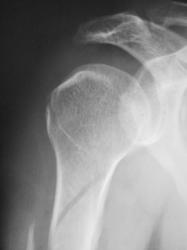

Травма. Пациент направлен врачом хирургом на рентгенографию плечевого сустава.

Что посоветуете уважаемые коллеги?

Спиральный перелом со смещением. А что в локтевом суставе? Мне кажется, что спираль продолжается дистальнее.

А что по "поводу головки" плечевой кости в "районе большого бугорка".

Думаю, что это начало спирали.

А еще это похоже на перелом по типу Хилл-Сакса большого бугорка.

Мне кажется, что импрессионного перелома бугорка (повреждение Хилл-Сакса) здесь нет. При данном повреждении импрессия более выражена. Типичный перелом Хилл-Сакса выглядит примерно так.

Хотя, конечно, аксиальная проекция всё бы расставила по своим местам. На мой взгляд, второго перелома в области бугорка здесь нет.